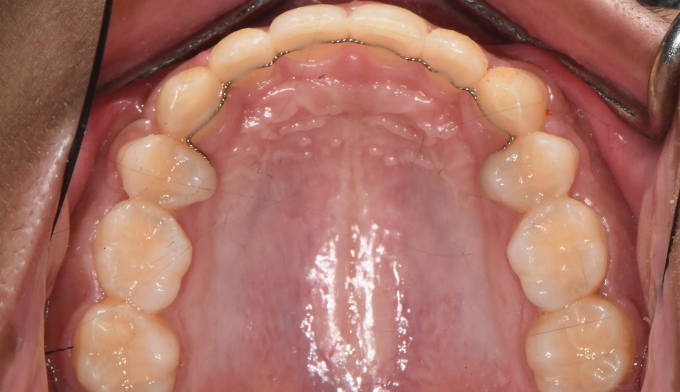

덧니가 심한 학생들, 특히 중,고등학생들을 보면 안타까울때가 종종 있습니다.

조금 더 이른나이에 교정을 시작하였더라면 무리하게 발치하지 않고도 충분히 치아를 가지런하게 할 수 있었을 텐데 라는 생각을 지울수가 없습니다.

이번 케이스도 뒤늦게 송곳니가 덧니로 나오는것을 확인하고 치아교정을 하고자 내원한 중학생입니다.

부족한 공간이 꽤 많고, 입도 돌출되어 보여서 어쩔수 없이 발치교정을 계획하였습니다.

총 치료기간은 23개월입니다.